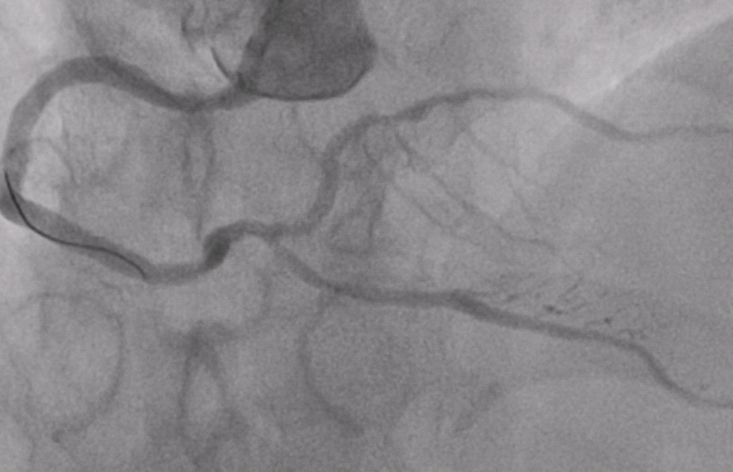

术后复查冠脉显影正常

陈先生入院后,潘宏伟主任团队对其病情进行了全面评估,制定了详细周密的诊疗计划,于1月27日行介入支架治疗开通了几乎完全闭塞的前降支血管,术后效果“立竿见影”,陈先生的胸闷症状立马消失了。由于陈先生冠脉多支多处弥漫性狭窄严重,要想修复所有的血管还需要在多处植入药物球囊,手术难度较大,加上年后就可以享用集采的价格,于是建议他调理两月再来。近日,陈先生从遥远的新疆再次打“飞的”来长沙行第二次手术,4月12日潘宏伟主任团队采用了支架+药物球囊的组合方式,完美的修复了非常复杂的冠状动脉,术后经过精心护理,陈先生于4月15日康复出院。